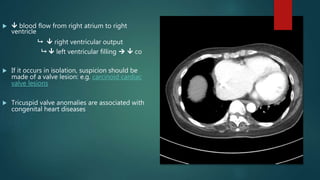

  blood flow from right atrium to right

ventricle

  right ventricular output

  left ventricular filling   co

 If it occurs in isolation, suspicion should be

made of a valve lesion: e.g. carcinoid cardiac

valve lesions

 Tricuspid valve anomalies are associated with

congenital heart diseases

 usually occurs together with aortic or

mitral stenosis

 may be due to rheumatic heart

disease (<5%)

 On CXR, the main radiological sign is

right atrial enlargement, which can be

appreciated on frontal view